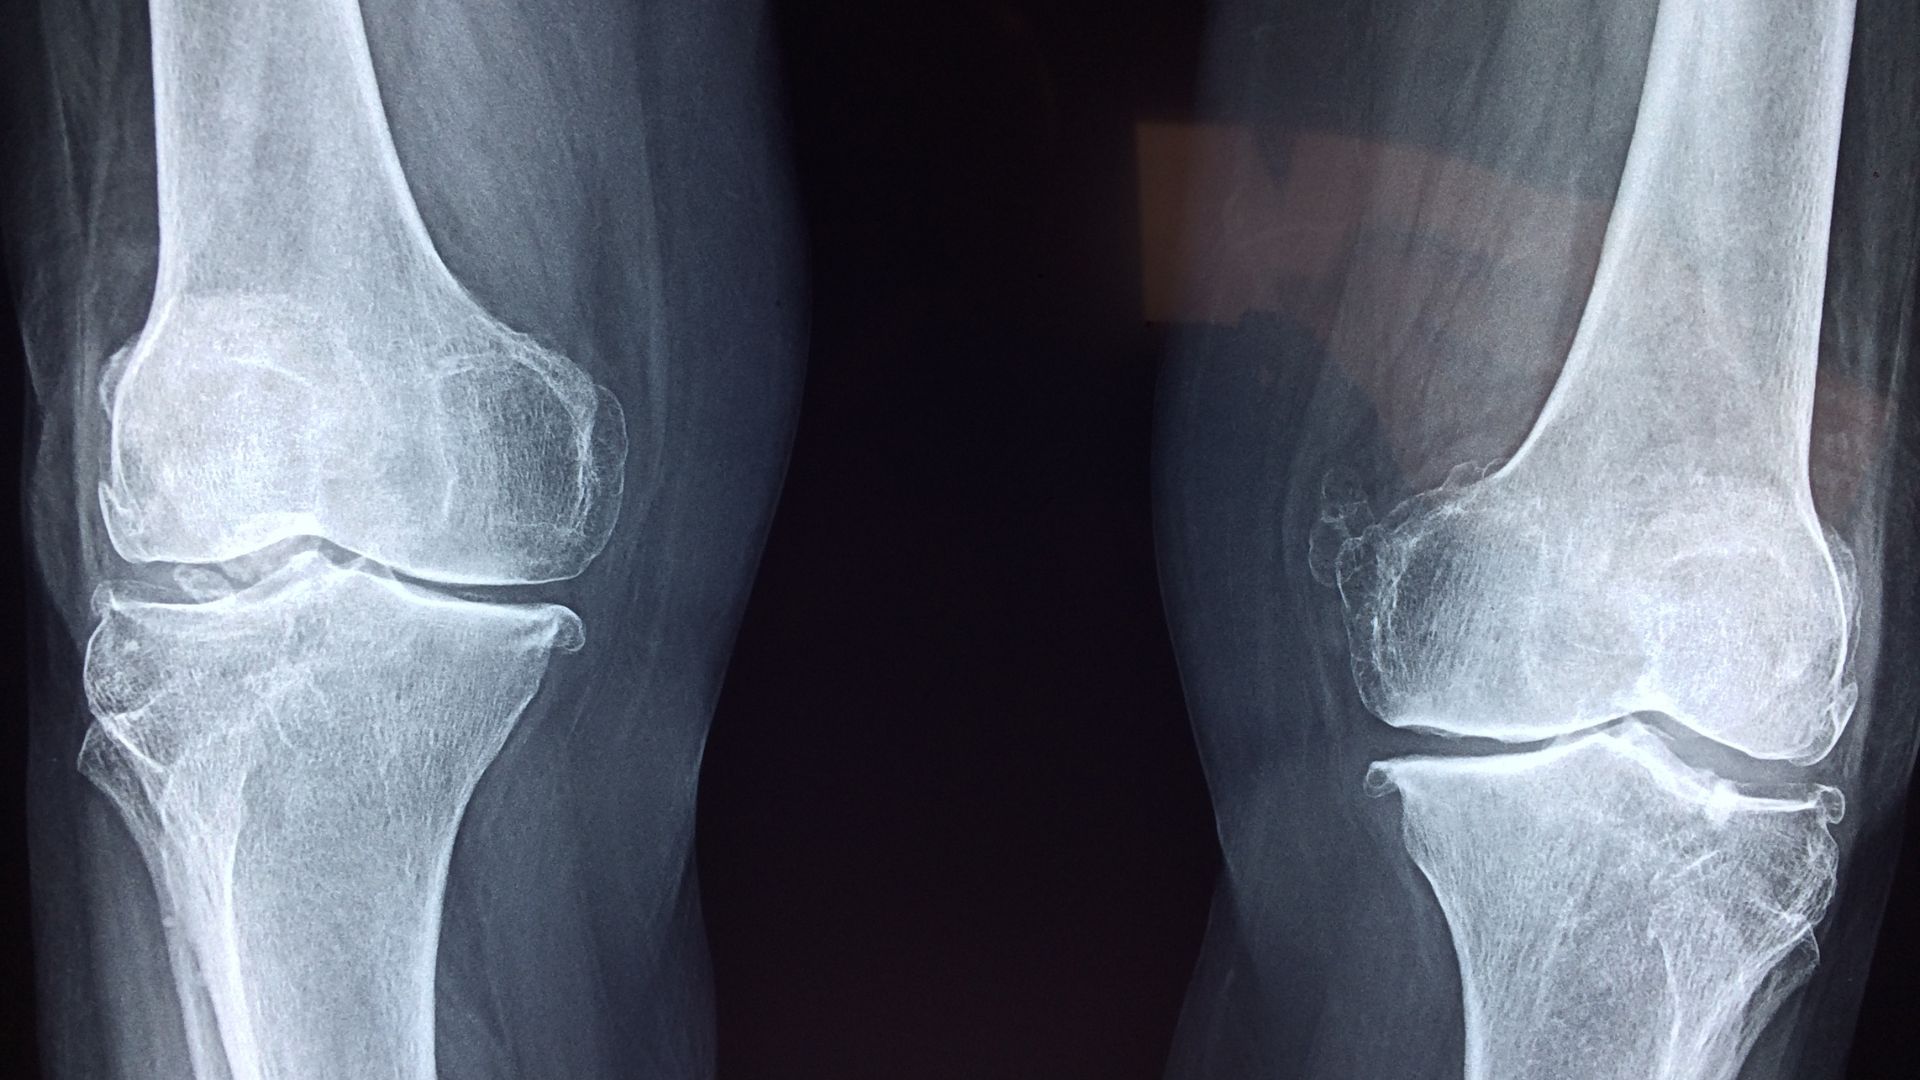

In-house diagnostic services allow healthcare providers to perform essential tests and scans right within their own facilities. These services commonly include blood tests, X-rays, ultrasounds, and MRIs, all of which play a key role in identifying and monitoring arthritis. Having everything under one roof means healthcare teams can collaborate closely, ensuring seamless communication about patient findings.

Recent years have seen strides in diagnostic technology, including the integration of artificial intelligence and automation into image analysis. These innovations help detect subtle joint changes that might be missed during manual reviews, leading to earlier interventions.